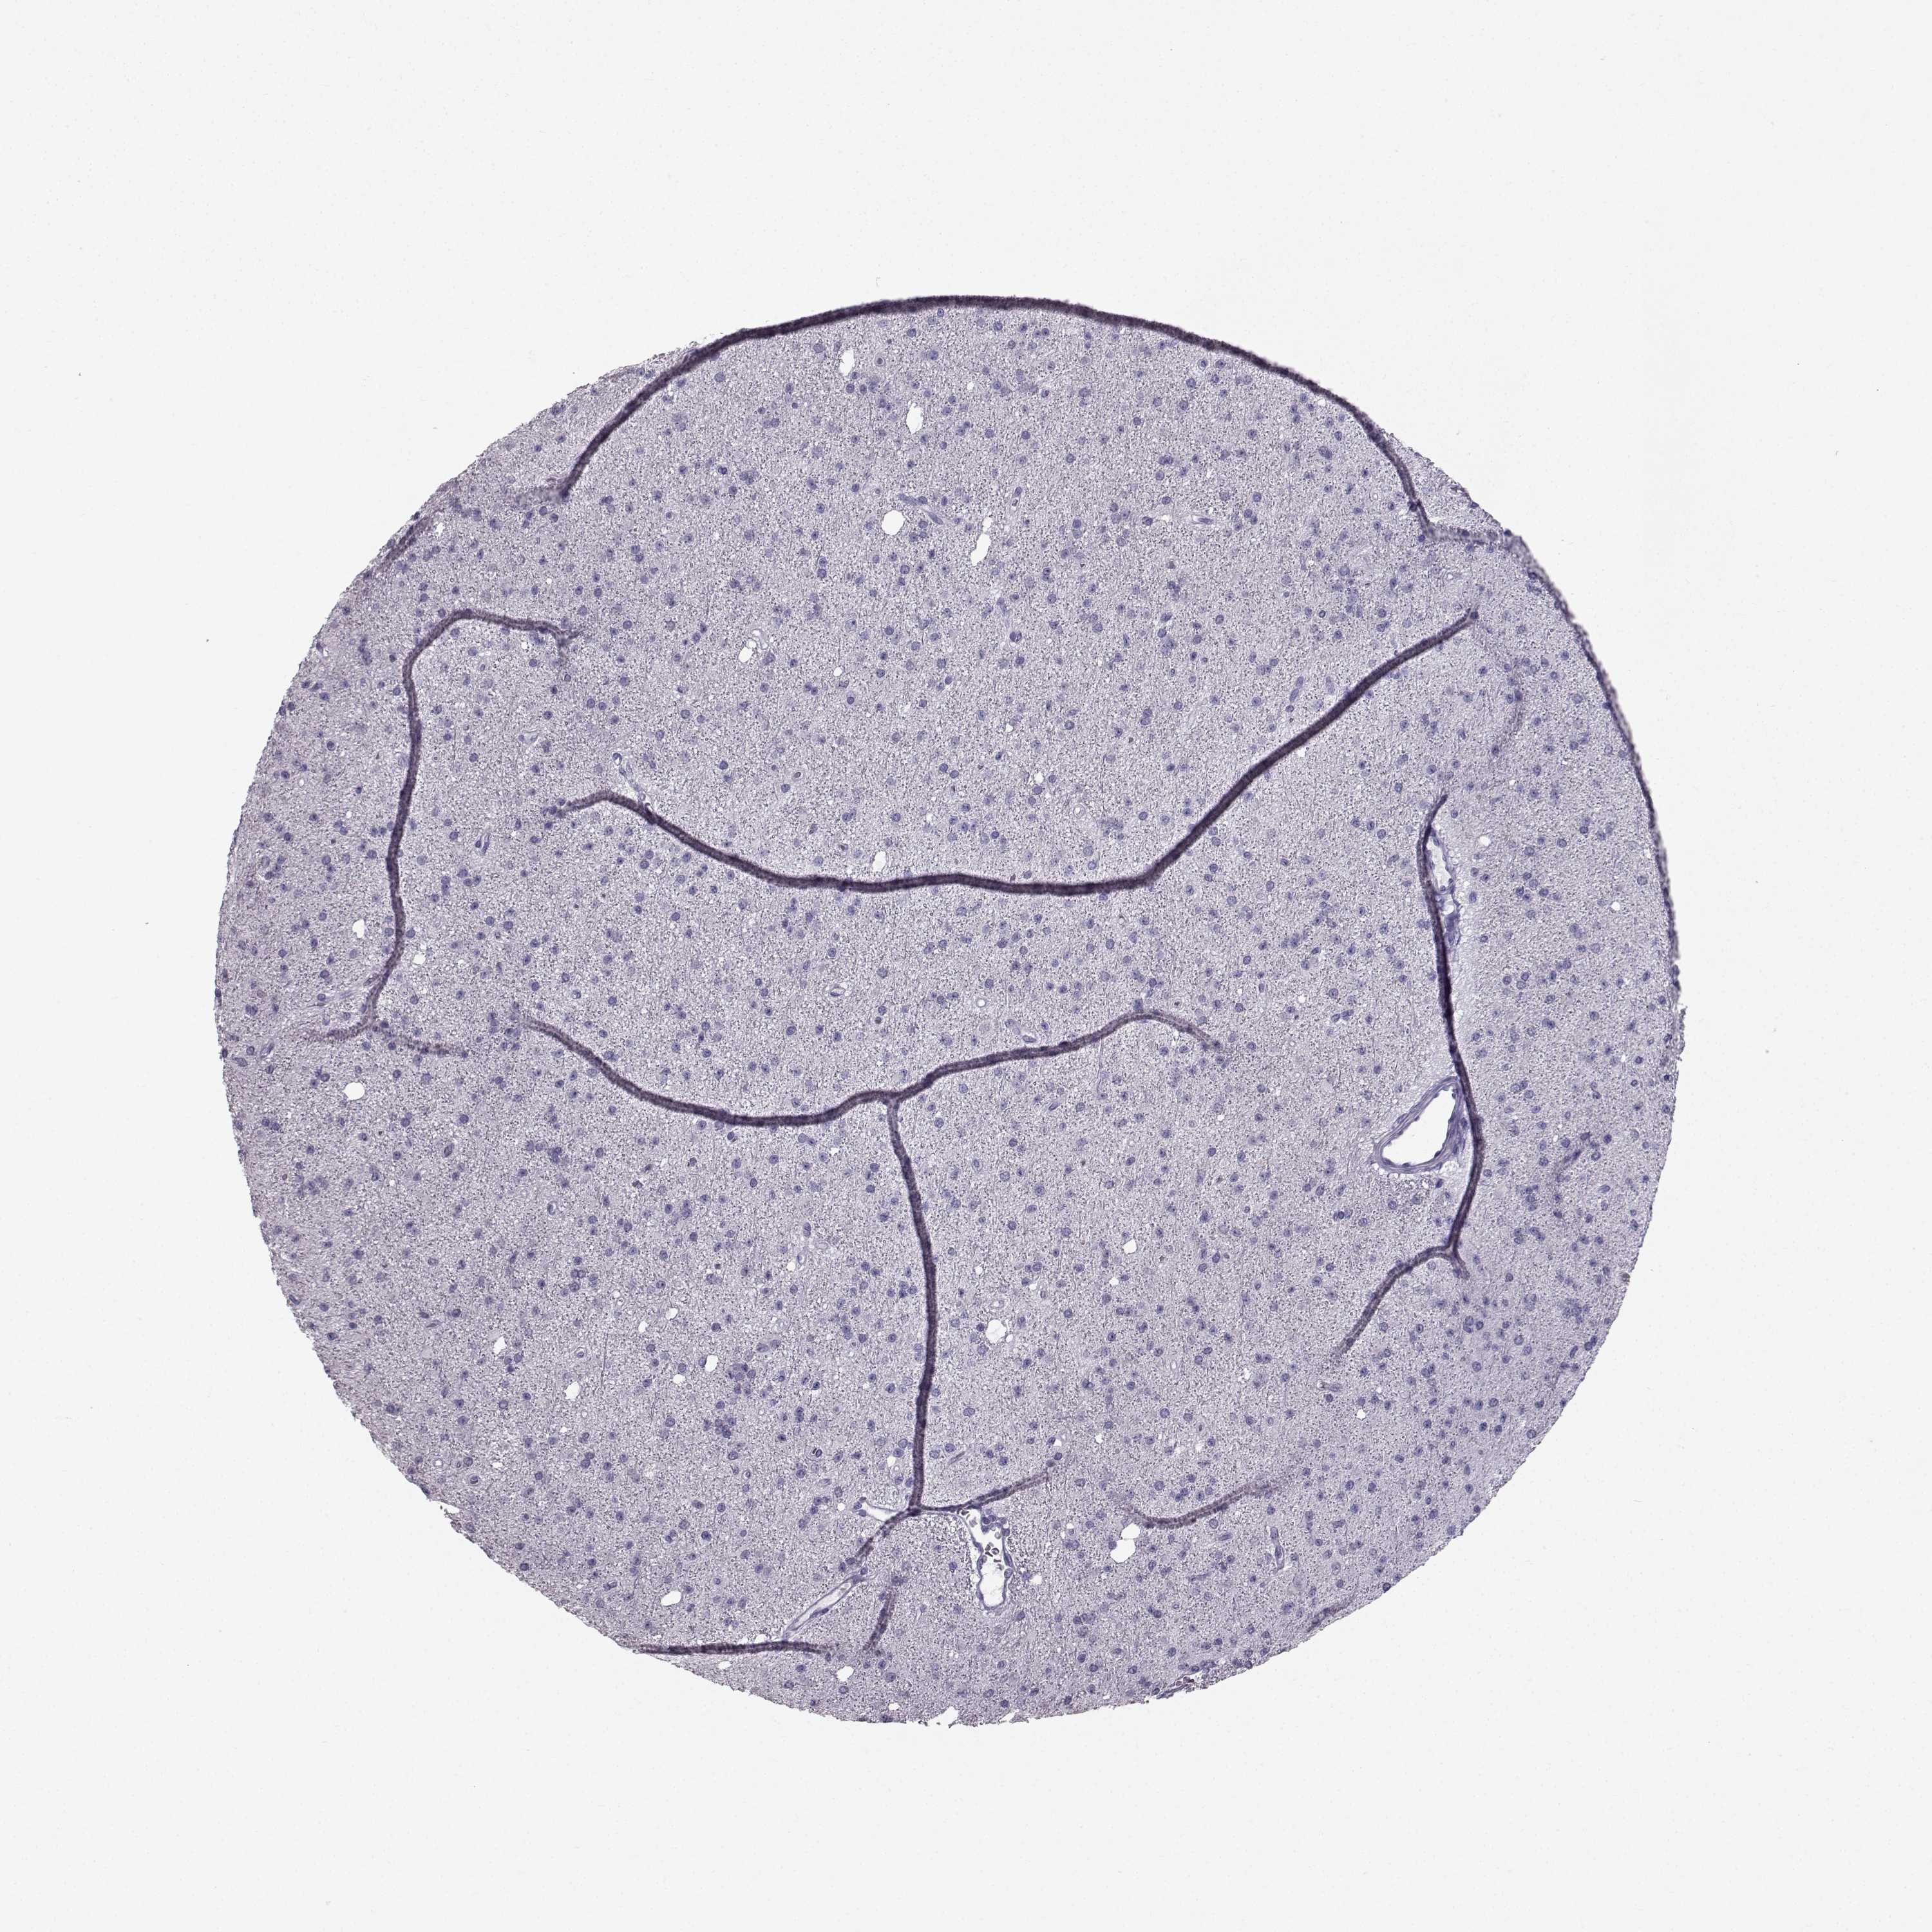

GLIOMA - Protein expressioni

A mouse-over function shows sample information and annotation data. Click on an image to view it in a full screen mode. Samples can be filtered based on level of antibody staining by selecting one or several of the following categories: high, medium, low and not detected. The assay and annotation is described here.

Note that samples used for immunohistochemistry by the Human Protein Atlas do not correspond to samples in the TCGA dataset.

Antibody stainingi

Antibody staining in the annotated cell types in the current human tissue is reported as not detected, low, medium, or high, based on conventional immunohistochemistry profiling in selected tissues. This score is based on the combination of the staining intensity and fraction of stained cells.

Each image is clickable and will lead to virtual microscopy that enables deeper exploration of all samples and also displays staining intensity scores, fraction scores and subcellular localization as well as patient and tissue information for each sample.

Antibody HPA055162

Staining

High

Medium

Low

Not detected

Intensity

Strong

Moderate

Weak

Negative

Quantity

>75%

75%-25%

<25%

None

Location

Nuclear

Cytoplasmic/membranous

Cytoplasmic/membranous,nuclear

Glioma, malignant, Low grade

Glioma, malignant, High grade